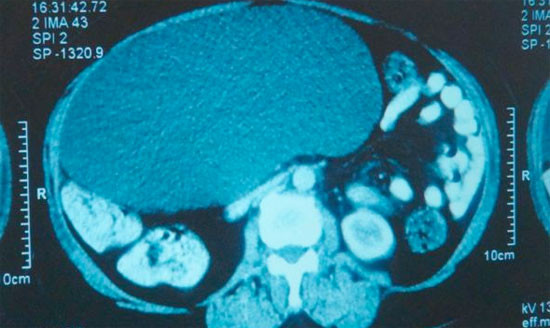

Abone olKONYA'da karın şişliği ve ağrısı şikayetiyle özel bir hastaneye başvuran 5 çocuk annesi, 63 yaşındaki Emine Karadağ'ın karnından futbol topu büyüklüğünde pankreas kisti çıktı.

Emine Karadağ, son 1 ayda karnında şişlik ve ağrı olunca Özel Farabi Hastanesi'ne başvurdu. Hastanede yapılan tetkiklerde Karadağ'ın karnında pankreas kisti olduğu saptandı.

Bunun üzerine Karadağ'ın karnındaki 30 santimetre çapında 4 kilo ağırlığındaki kist, yapılan başarılı bir ameliyatla alındı.

"Hastamız karın ağrısı ve şişkinliği şikayetiyle başvurdu. İlk muayenede karnını dolduran 30 santimetre çapında büyük bir kitle olduğunu tespit ettik. Çok nadir görülen ve toplumda 400 kişi de 1 görülen bir hastalık. Bu boyuta ulaşanını çok az rastlanır. Yaklaşık 4 kilogram civarında bir kütleydi içerisinden de 4 litreya yakın sıvı çıkardık. Hastamızın genel durumu şu anda iyi."